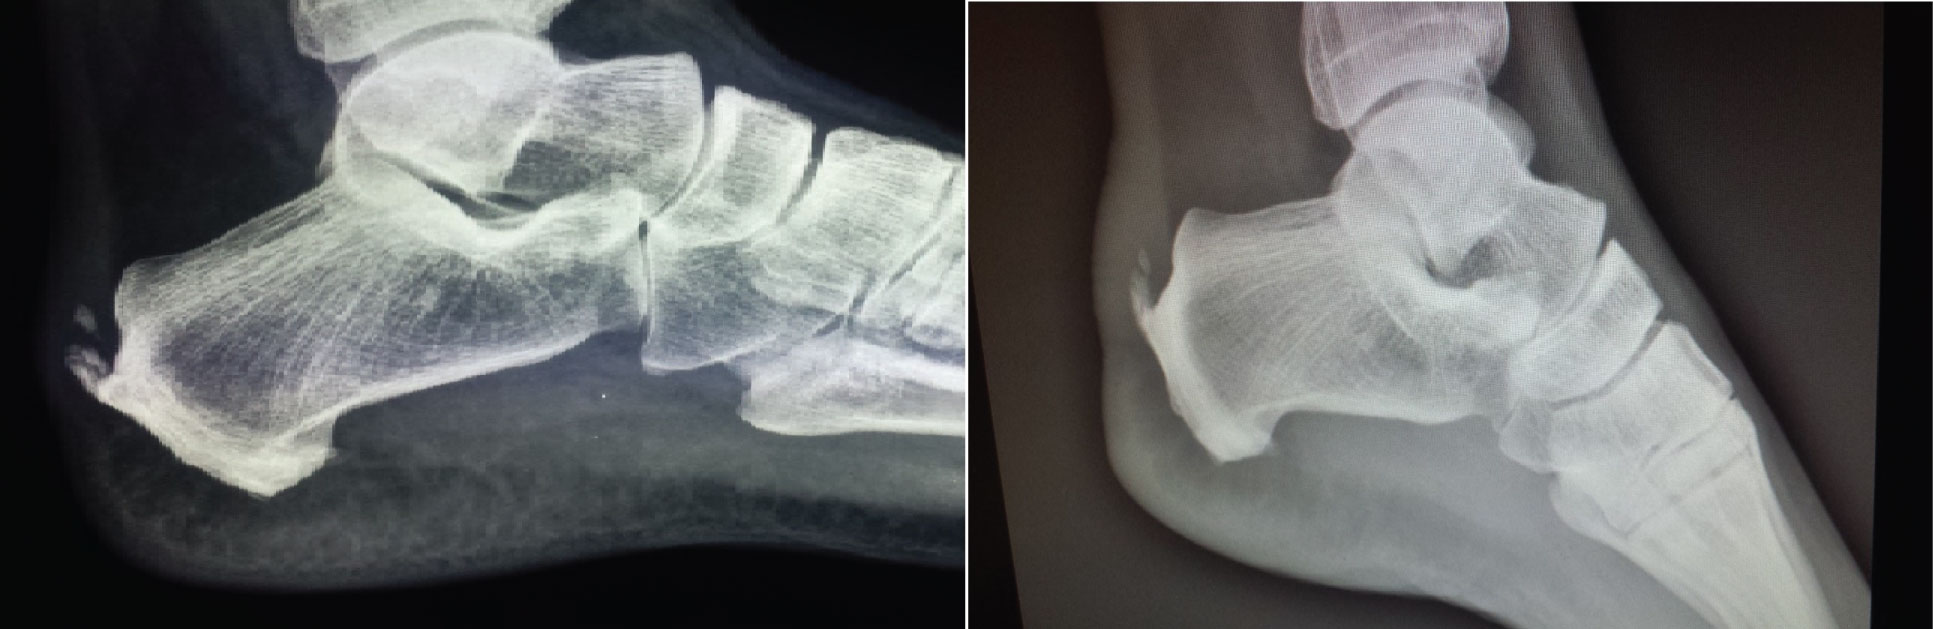

With regard to the change in millimeters (mm) of the calcification, all of the patients showed a decrease in the size of calcification. The radiological change in Achilles CT was significant; decreased from 10 ± 5.3 to 5.3 ± 5.22 mm (p = 0.0186), (Table 2, Figures 2, Figure 3, Figure 4, Figure 5 and Figure 6).

Figure 2: Case 1: In a 50-year-old female, after 10 sessions of treatment, pain decreased from 8/10 to 1/10 and size of calcification decreased from 12 to 6 mm. View Figure 2

Figure 3: Case 2: In a 38-year-old female, after 20 sessions of treatment, pain decreased from 10/10 to 2/10 and size of calcification decreased from 3 to 2 mm. View Figure 3

Figure 4: Case 3: In a 47-year-old male, after 20 sessions of treatment, pain decreased from 7/10 to 4/10 and size of calcification decreased from 10 to 0 mm. View Figure 4

Figure 5: Case 4: In a 57-year-old female, after 15 sessions of treatment, pain decreased from 9/10 to 4/10 and size of calcification decreased from 9 to 4 mm, evaluated by sonography. View Figure 5

Figure 6: Case 5: In a 57-year-old female, after 15 sessions of treatment, pain decreased from 5/10 to 0/10 and size of calcification decreased from 6 to 0 mm, evaluated by sonography. View Figure 6